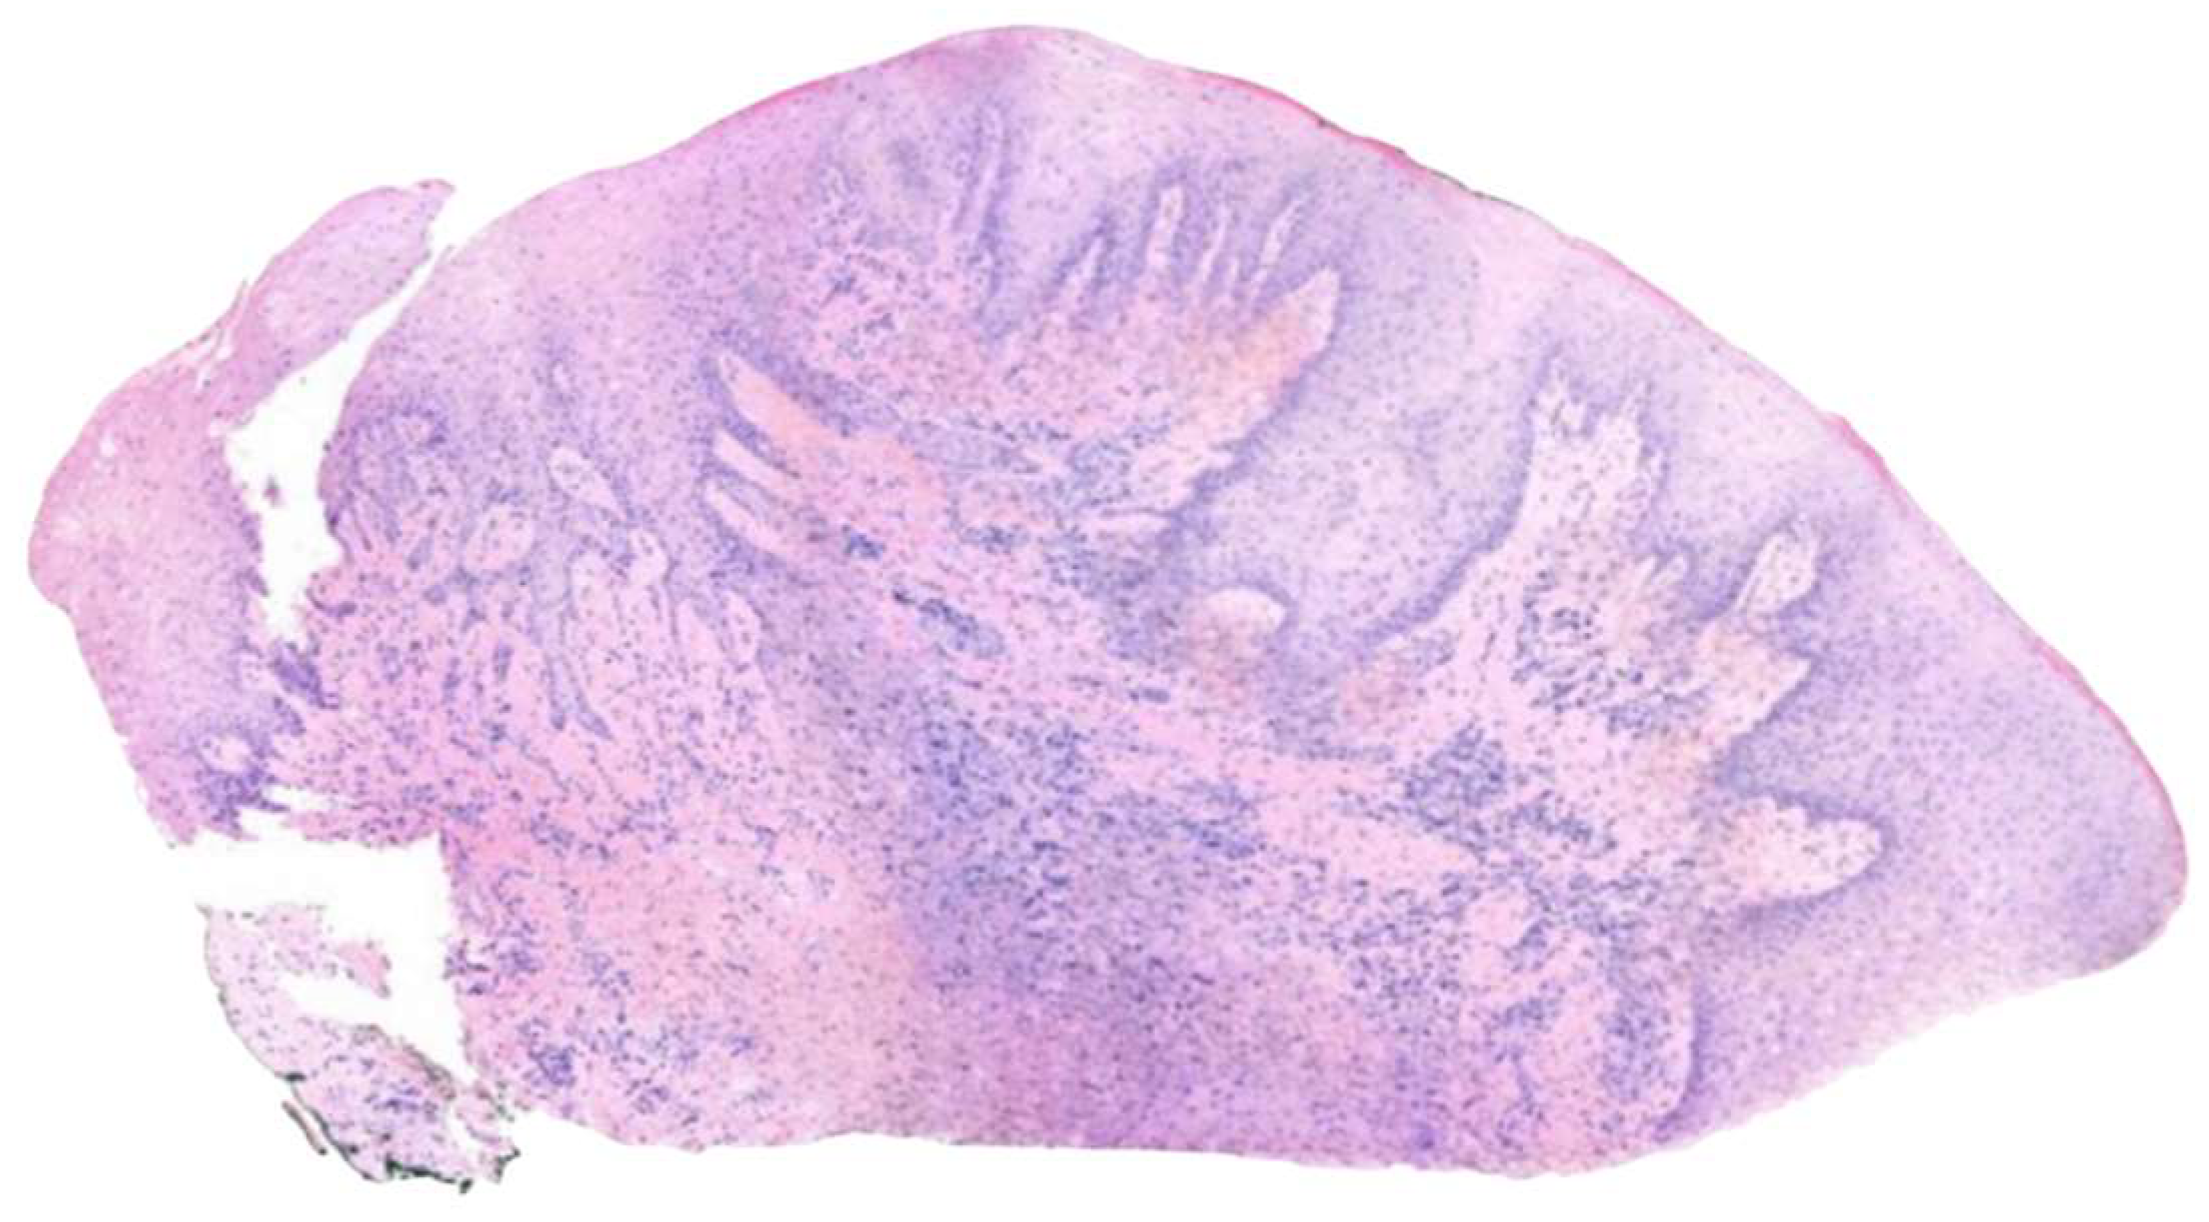

2.2. Histopathological Examination